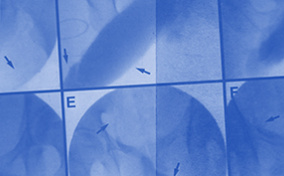

A Venous Leak Could Be the Reason for Erectile Dysfunction

If you're able to attain but not maintain an erection, faulty veins might be the problem.